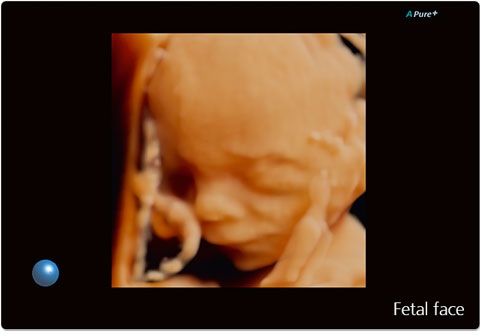

Система Aplio 300 – идеальный вариант для тех, кому нужна надежная и эффективная работа оборудования в ежедневной практике. Эта высокопроизводительная, универсальная и экономичная система предлагает получение качественных изображений с впечатляющей глубиной и детализацией в самых разных областях медицины.

• Трехмерная эхография в реальном времени с использованием специализированных 4D датчиков;

• Программа анализа сердца плода в трех проекциях в реальном времени 4D Stick;